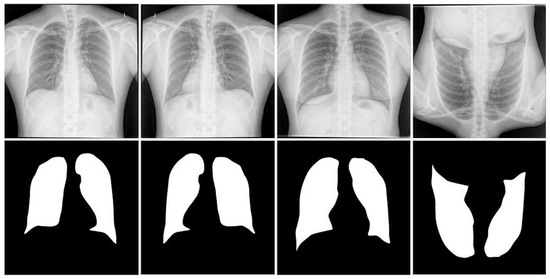

Visualization. We present our findings by comparing the qualitative results on the JSRT dataset, MC dataset, and Shenzhen dataset, as shown in Figure 9. In the figure, the squares represent the comparison of the difference areas of segmentation results for different data sets.

Figure 9.

Quantitative results of lung field segmentation on the JSRT, MC, and Shenzhen datasets.

We used the CNN-based method U-Net, the Transformer-based Swin-Unet, and UCTransNet, and to verify their ability to recognize semantic features, we visualized the feature maps for each decoder stage. Looking at the segmentation results, we can find that these methods may have suffered from over-segmentation or lossy segmentation. For the first experiment, there was under-segmentation in the U-Net network: from the above figure, we can see that, in the upper region of the lung field of the JSRT image and the middle region of the lung field of the MC image, the segmented edges are missing compared with the true values, and the lower region of the lung field of the Shenzhen image also shows lossy segmentation, which was due to the fact that the downsampling process weakened the detail information and the upsampling process made it difficult to fully recover the original features and spatial information. Even though the U-Net network employs cross-layer connections to preserve certain low-level features, this mechanism still cannot solve the lossy segmentation problem well because of the limitations imposed by the characteristics of the network itself and the multi-level information transfer. Comparatively, in the second experiment, the Swin-Unet network showed over-segmentation: in the above figure, we can see that over-segmentation occurs in the lower-right region of the JSRT lung field image, the middle region of the MC lung field image, and the lower-left region of the Shenzhen lung field image, which was due to the poor generalization ability of the model, and the associated region was segmented into multiple unrelated parts. This led to information loss and redundancy, which decreased the performance and efficiency of the model on lung medical image processing and increased the false positive rate and uncertainty of the likelihood analysis. In addition, in the third experiment, the UCTransNet network made an error in lung prediction and did not detect its central location correctly. We can see that there was a slight over-segmentation in the right region of the JSRT lung field image, the central region of the MC lung field image, and the central region of the Shenzhen lung field image, which may have been due to the inability of the model to obtain enough semantic features to fully convey the information. As shown in the figure, in the last experiment, our proposed TransCotANet, on the other hand, was able to fully and dynamically perceive the contextual multi-scale semantic feature information and was able to correctly segment the left and right lung images with more reliable results and clearer boundaries. Therefore, it can be concluded that our method could not only effectively learn semantic information for medical image segmentation, but also improve the segmentation performance and ensure the accuracy of the segmentation results.